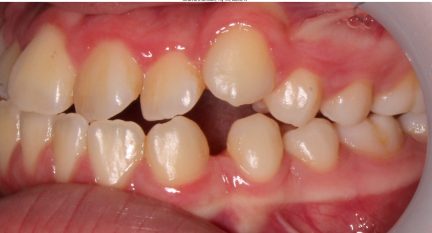

Classe III, articulé postérieur, articulé antérieur, occlusion bout-à-bout, béance, arcades asymétriques, déviation de la ligne médiane mandibulaire, chevauchement, rotations, espacement

État initial